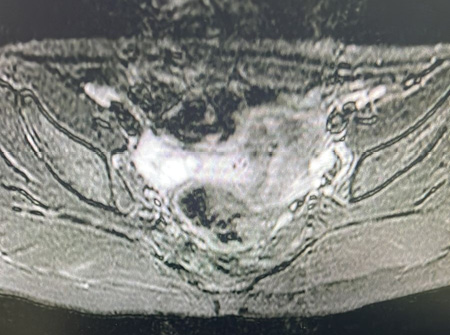

Выполнено инструментальное обследование: ретроградное рентгеноконтрастное исследование нижних отделов толстой кишки (ирригография) (рис. 1), магнитно-резонансная томография (МРТ) крестцово-копчиковой области (рис. 2), в ходе которого на основании клинической картины (хронического толстокишечного стаза), наличия аномалий строения анального канала (стеноз), а также выявленных аномалий дистальных отделов позвоночника установлен диагноз: врожденный стеноз анального канала в составе синдрома Куррарино, осложненное хроническим толстокишечным стазом, мегаректум.

Рисунок 2.

МРТ крестцово-копчиковой области — переднее менингоцеле с множественными разнокалиберными кистами и стромальным компонентом

Figure 2.

MRI of the sacrococcygeal region — anterior meningocele with multiple cysts of different sizes and a stromal component